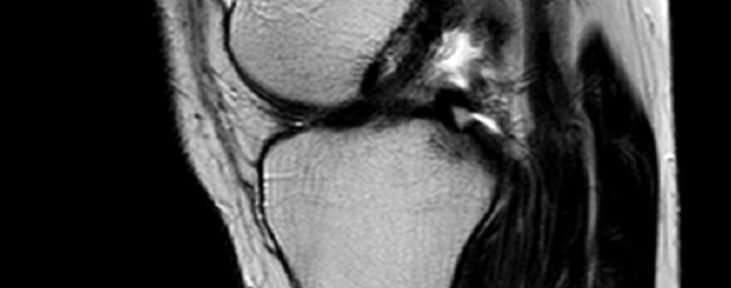

ACL Tear Natural Healing Case Report #50Case 50 | Natural Healing of Complete ACL Rupture: From Severe Ihara Type IV to Perfect Regeneration (ACLOAS Grade 0)

ACL Natural Healing Case Report #50: Most Severe Ihara …